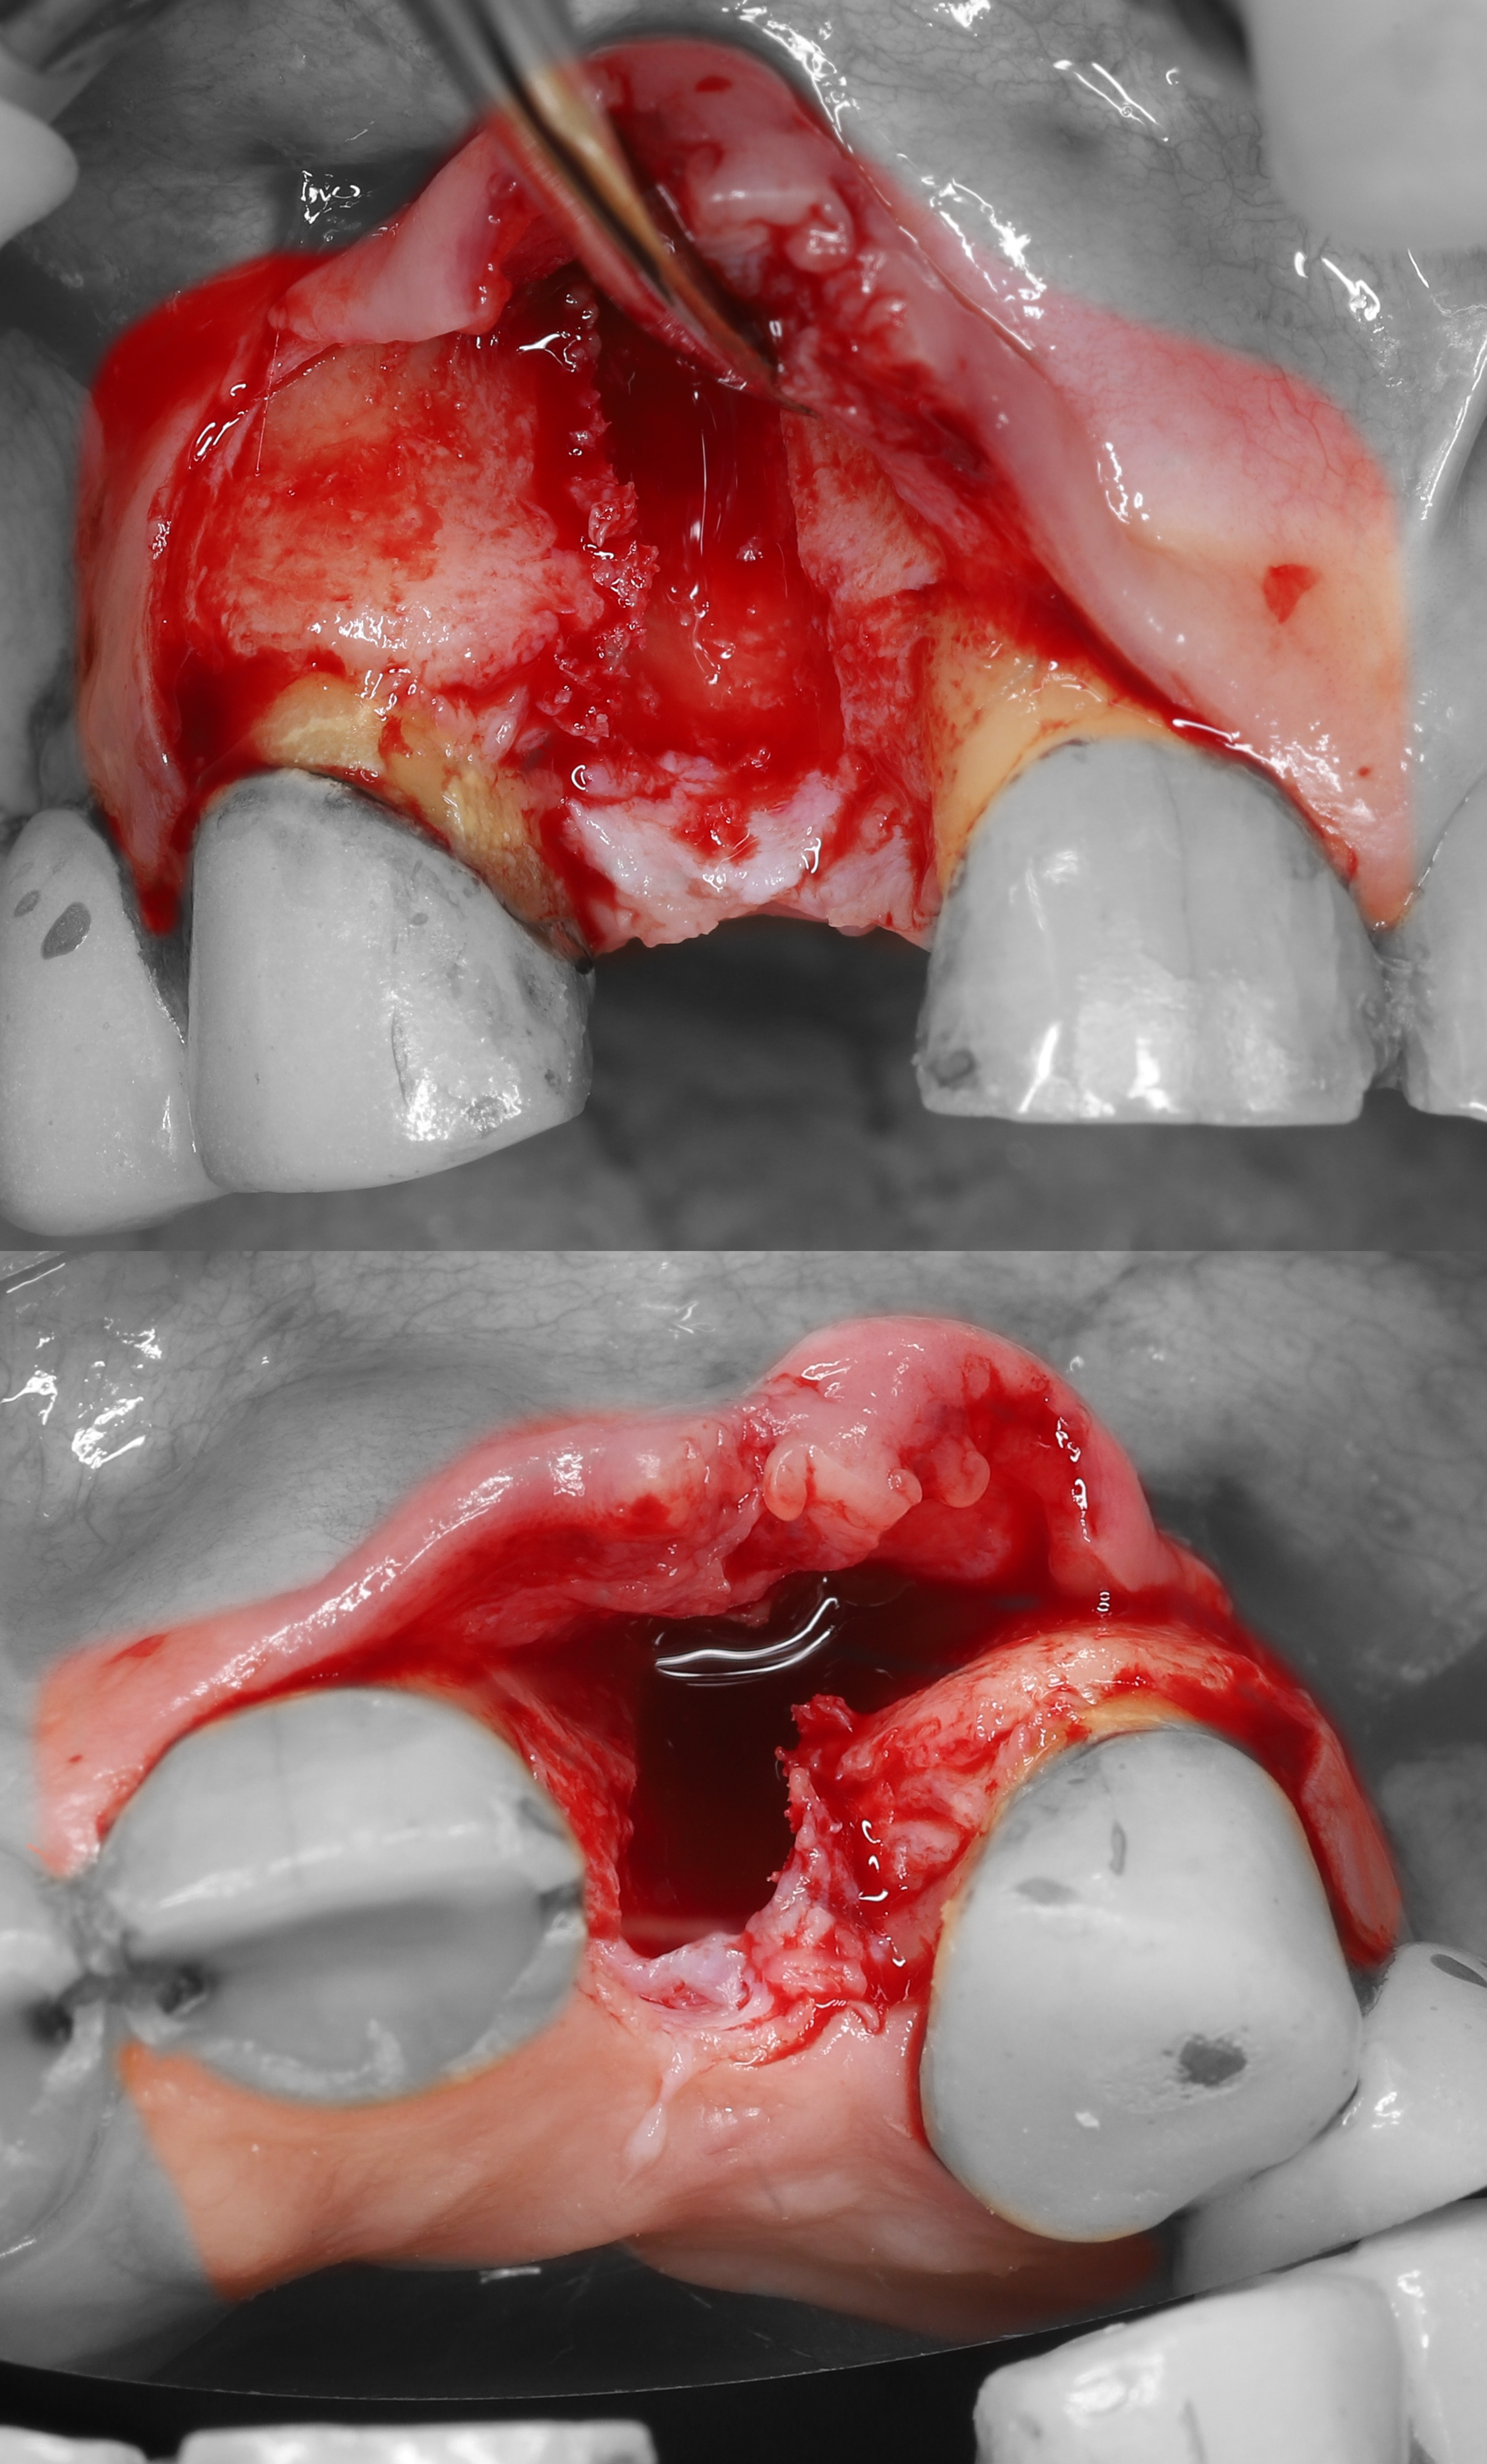

2) Проведены крестальный и вертикальный дистальный разрезы, отслоен СНЛ.

3) Проведена остеотомия имплантантного ложа.

5) Из области бугра ВЧ был получен кортикально-губчатый трансплантат.

6) Костный графт был фиксирован в области вестибулярного дефекта с помощью прижатия 2-мя пинами.